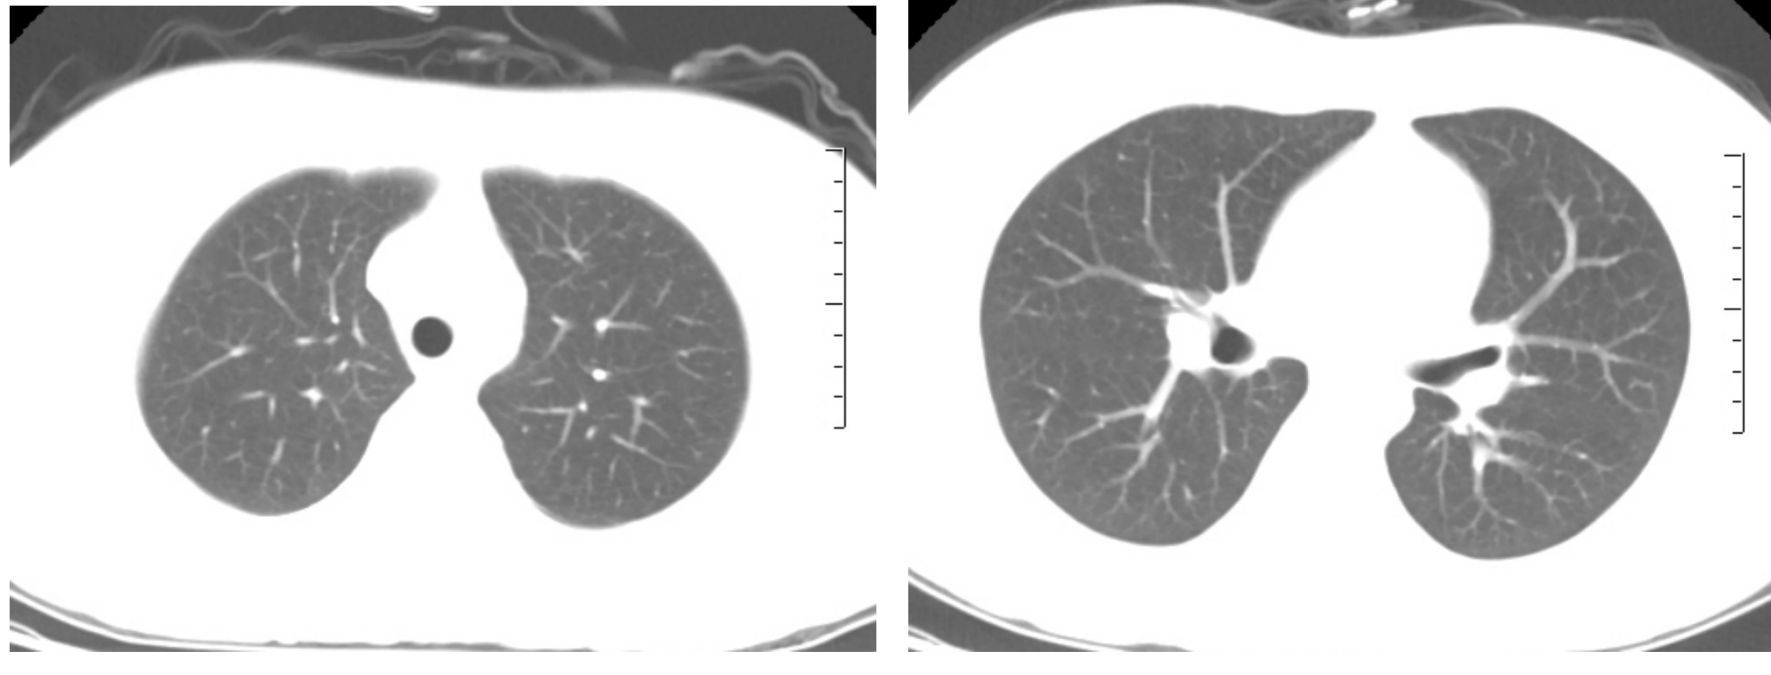

患者,女,24岁,主因“发热、干咳20余天”入院。外院抗生素治疗效果差。既往肾病综合征,口服激素。查体:T 38 ℃、P 105次/min,RR 20次/min,BP 102/73 mmHg(1 mmHg=0.133 kPa),双肺未闻及啰音。辅助检查:WBC 1.52× 109 L-1、NE 78.3%;CRP 71 mg/L;ALT 248 U/L、AST 118 U/L;动脉血气(未吸氧):pH 7.44,PaCO2 34 mmHg,PaO2 69 mmHg;胸部平片未见异常。入院后美罗培南治疗3 d,未见好转,呼吸困难进行性加重,I型呼吸衰竭。第3日胸部CT提示双肺间质弥漫渗出,部分实变(图 1),病原不明确,调整抗感染方案:美罗培南、莫西沙星、磺胺、卡泊芬净、更昔洛韦250 mg/12 h、甲强龙40 mg/d、丙种球蛋白。第6日症状明显好转,复查胸部CT较前明显吸收(图 2),此时回报PCT、血培养、G试验、GM试验、呼吸道病原菌培养均阴性;CD4、CD8及CD4/CD8显著下降;肺泡灌洗液CMV-DNA 9.4×105 拷贝/mL,血清CMV-DNA 4.35×104 拷贝/mL,考虑巨细胞病毒肺炎诊断明确,维持更昔洛韦、甲强龙治疗3周,1月后胸部CT示渗出及实变完全吸收(如图 3)。

图 2 第6日胸部CT